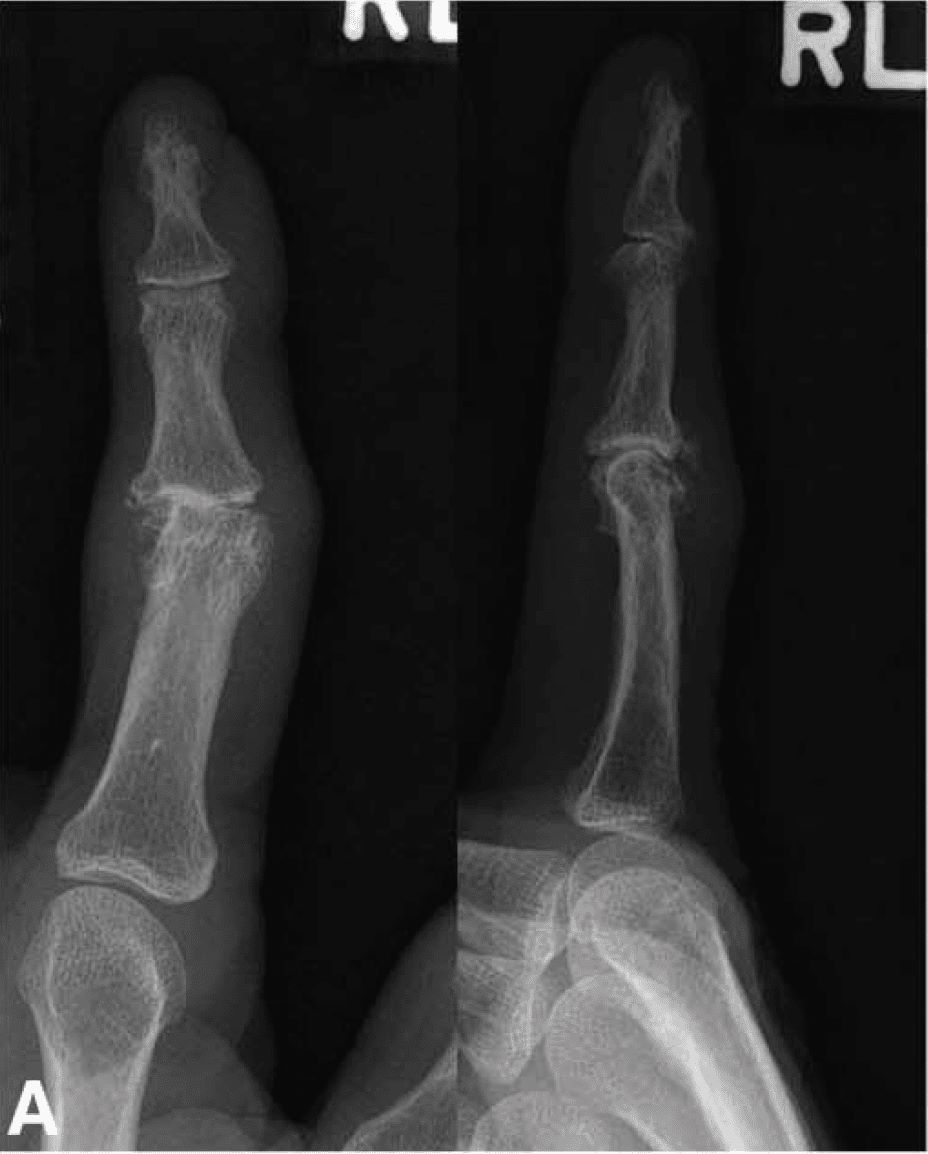

X-rays Showing Finger With Arthritis

X-rays of a patient with severe arthritis of the proximal interphalangeal (PIP) joint. This patient also has some arthritis of the distal interphalangeal (DIP) joint.

Reproduced from Carlson Strother CR, Moran SL, Rizzo M. Small Joint Arthroplasty of the Hand: An Update on Indications, Outcomes, and Complications. J Am Acad Orthop Surg. 2023;31(15):793-801. doi:10.5435/JAAOS-D-23-00034